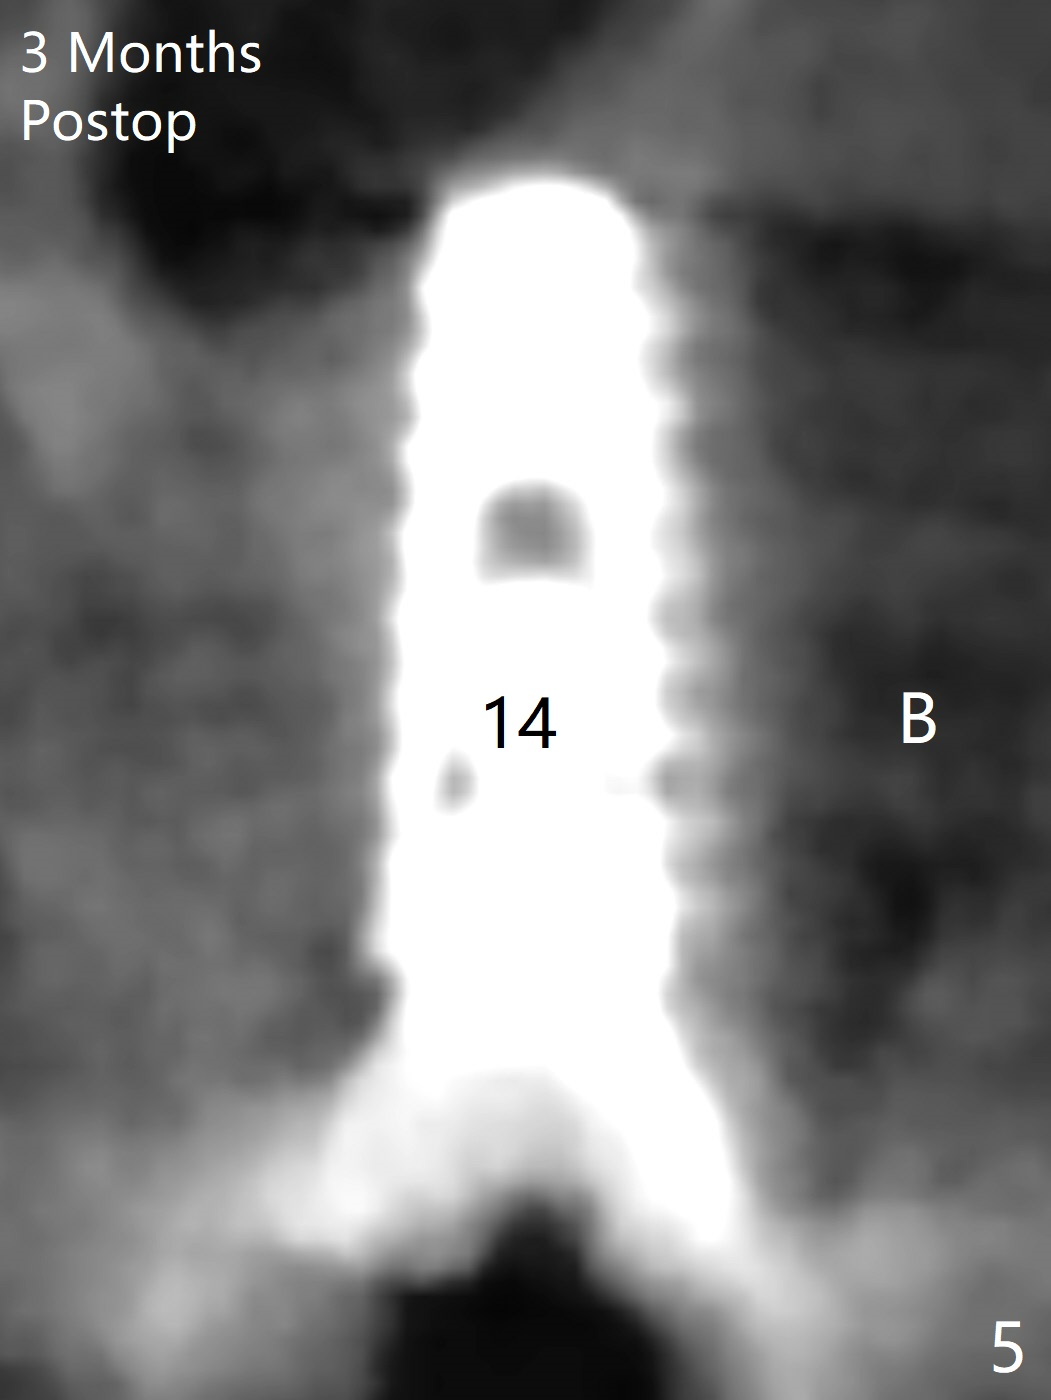

Initial osteotomy in the septum of the tooth #14 is 9 mm, approximately 2 mm from the sinus floor (Fig.1). Subsequent osteotomy depth is 11 mm, followed by insertion of a 4.5x11 mm dummy implant (Fig.2). After use of Magic Drill (MD) 4.8 mm for 9 mm, a 5x11 mm IBS implant is placed with sinus lift without additional bone graft (Fig.3 *). In contrast, autogenous bone (from MD) and Vanilla Graft are meticulously placed in the remaining socket (+) before and after placement of a 6.5x5.7(2) mm abutment. An immediate provisional is fabricated to close the sockets. There is buccal tenderness 1-3 months postop. There is distopalatal implant thread exposure. A healing abutment (5.5x2 mm) is placed. CT confirms thin buccal plate (Fig.4,5). It appears that the implant should have been as palatal as possible. The tenderness remains for the next 2 weeks. When the healing abutment is removed, the implant seems to have been placed shallow, ~ 1 mm subgingival (Fig.6). With local anesthesia, the implant is reversed to clean the coronal threads with Titanium brush and copious irrigation (Fig.7). The implant is then placed ~4 mm subgingival (Fig.8) and slightly subcrestal (Fig.9,10). It appears that the postop bone loss (Fig.9 *, as compared Fig.1,2) makes the implant look to be placed too shallow. When the implant is being placed deeper, the buccal plate feels intact. The early periimplantitis is apparently due to postop bone loss more than buccal placement, although certain degree of buccal bone resorption must occur. A 6x4 mm healing abutment is placed. Left facial swelling develops 2 days post implant elevation (Fig.11,12, as compared to preop (Fig.13)). The left maxillary sinus cloud (Fig.12) appears to be a false positive finding, since the same feature exists prior to implant elevation (Fig.13). Both sinuses look clear prior to implant elevation (Fig.14). Amoxicillin switches to Augmentin and Flagyl, since the patient is reluctant to have the implant removed. Finally the sinus infection is under control. The patient feels left facial swelling 9 months postop (5 months post elevation) and reports left nasal discharge ~ 1 month earlier. There is mild buccal plate tenderness. The implant seems to be buccally placed (Fig.15,16), although there is no significant change radiographically (Fig.17). The implant is removed with bone graft (Fig.18 *). To avoid complication and failure, an immediate implant at the upper 1st molar should be short and placed deep.